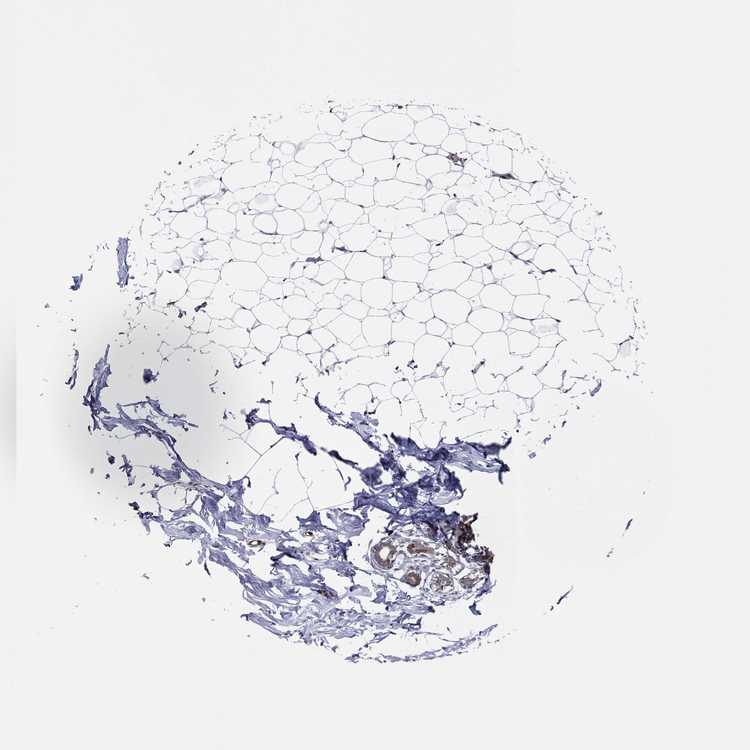

BREAST - Antibody stainingi

Antibody staining in the annotated cell types in the current human tissue is reported as not detected, low, medium, or high, based on conventional immunohistochemistry profiling in selected tissues. This score is based on the combination of the staining intensity and fraction of stained cells.

Each image is clickable and will lead to virtual microscopy that enables deeper exploration of all samples and also displays staining intensity scores, fraction scores and subcellular localization as well as patient and tissue information for each sample.

Antibody HPA014404Antibody CAB040581Antibody CAB080022

Adipocytes Not detectedNot detectedNot detected

Glandular cells Not detectedNot detectedNot detected

Myoepithelial cells MediumHighHigh